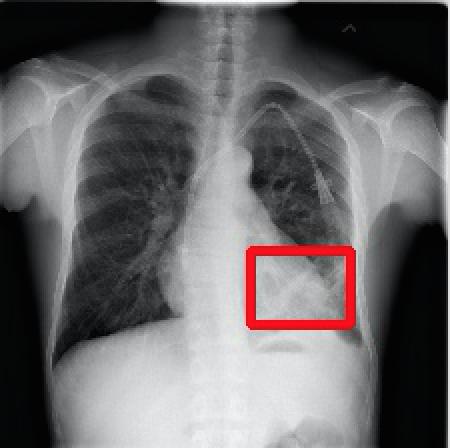

2017年CVPR的一篇“ChestX-ray8”论文[1]首次对医院留存的胸部CT数据库进行人工处理,并通过医学专家分别对8种疾病作标记,形成该领域首个标准的数据库,为胸部医疗的计算机辅助诊断打开了大门,也为后续的研究提供铺垫。CT数据库整理的效果如下图所示,其中红线框内为人工标注的疾病区域:

Atelectasis Cardiomegaly Effusion Infiltrate

Mass Nodule Pneumonia Pneumothorax

图2.1 胸部数据集示例

目前为止,数据集已经达到了14个疾病的分类结果,每张图的大小为1024×1024,少数图片附有由专家标注的病理区域,数据集共有112120张图片,来源于30805个不同的病人,其中51708张图片被标注有疾病,其余则为无病。可以看出无病的数据较多,对有病的特征学习可能较低,相关的学习加速收敛的方法将在2.4节讲解。